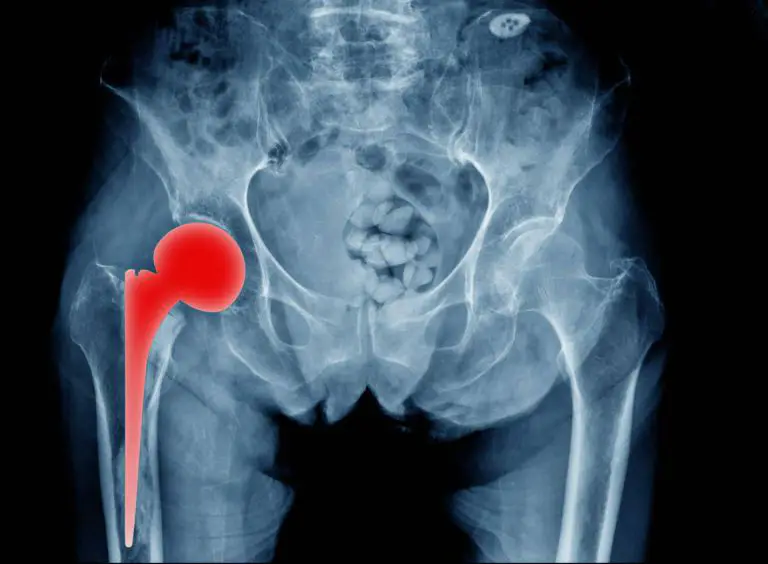

La artropatía degenerativa o artrosis es la enfermedad progresiva articular más frecuente en la actualidad porque afecta a más de 7.000.000 de personas en España.

Sobre la artropatía degenerativa explican que sus causas no están del todo claras. Pueden ser generadas por lesiones, accidentes o sobrecargas persistentes que van acumulando un deterioro progresivo en las articulaciones. También se relaciona con posturas incorrectas que algunas personas tienen de nacimiento y con factores hereditarios relacionados con la genética familiar.

La artropatía degenerativa es una patología crónica cuyos síntomas se manifiestan con rigidez y sensación de tensión en la articulación afectada. También son frecuentes los crujidos o chasquidos al moverse y la sensibilidad aumentada cuando el paciente se enfrenta a climas húmedos. Cómo es lógico, en muchos casos, el síntoma más incómodo suele ser el dolor.